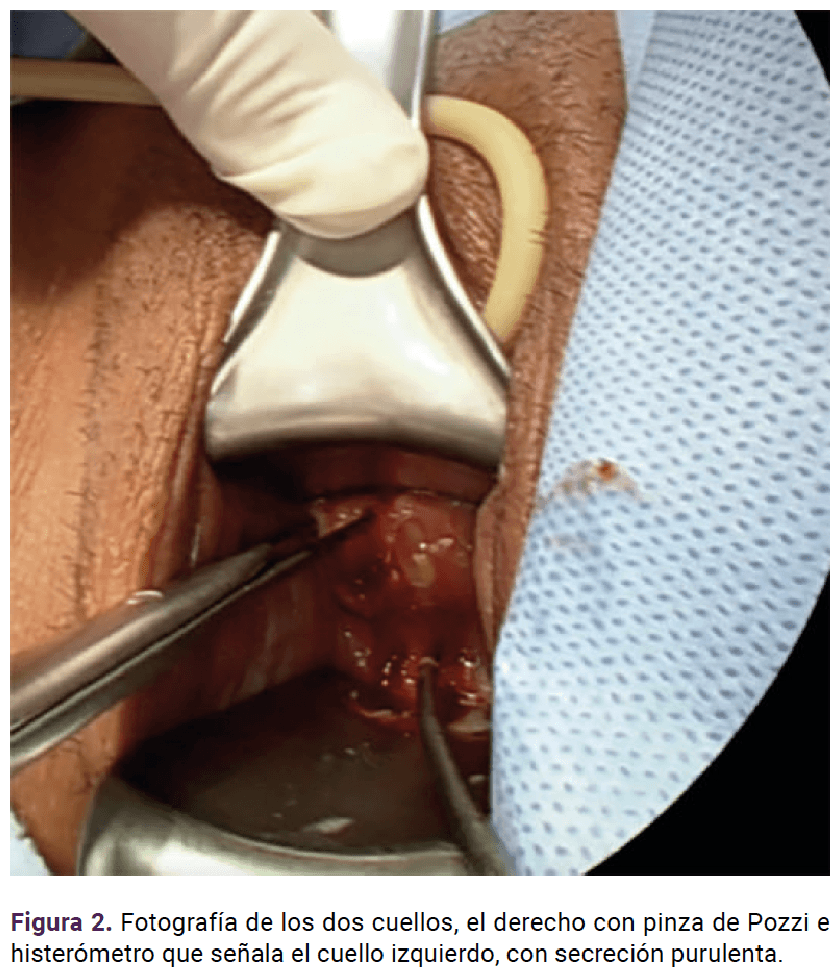

A la exploración con espejo se visualizaron dos cuellos. Del lado derecho se observó sangre y en el izquierdo secreción purulenta. El reporte microbiológico fue de Escherichia coli (betalactamasas de espectro extendido).

Cuatro meses después por persistencia del piometra (Figura 2) se le practicó una hemihisterectomía izquierda, por vía laparoscópica. (Figura 3).

<strong>Figura 2</strong>

Figura 2